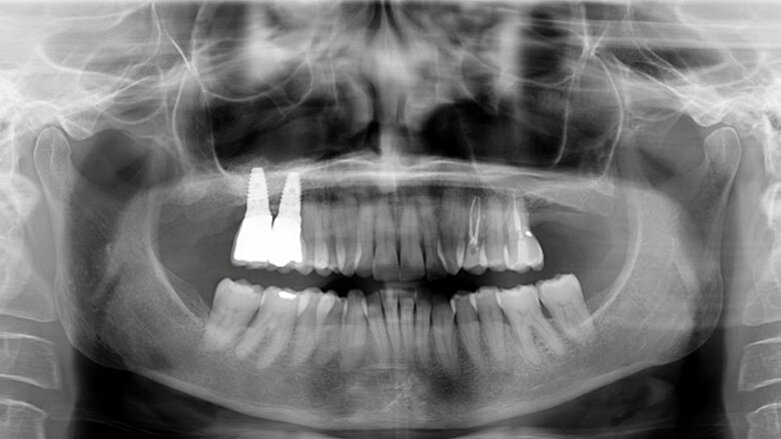

Materials and methods: Twenty-six wide-diameter implants with a rough surface over their entire length were inserted during 13 consecutive sinus lifts. Radiographic analysis was preoperatively requested for each patient. After Schneiderian membrane elevation, a magnesium-enriched hydroxyapatite (Mg-e HA) and collagen-based scaffold with a porous 3-D structure was used to prevent perforation during implant placement. Sinus grafting was performed using a biomimetic Mg-e HA. No membrane was used to cover the buccal window. The preoperative residual bone height ranged between 1 and 4 mm (mean value: 2.5 mm; SD: 1.0 mm).

In order to measure bone changes, the patients underwent panoramic radiographs after 2-year follow-up. Image analysis software calculated the grafted bone height changes at the level of the implant site, comparing preoperative and follow-up panoramic radiographs.

Results: No postoperative complications were observed. The mean ISQ value was 42.5 (SD: 2.7) at T0, 75.3 (SD: 8.2) at T1 and 81.5 (SD: 2.6) at T2. Statistically significant differences (P ≤ 0.005) regarding mean ISQ values were found between T1 and T0, as well as between T1 and T2. After 12 months of functional loading, only 1 implant was lost (cumulative survival rate: 96.15%). During the same observation period, the mean radiographic vertical height of the grafted sinus floor was 11.05 mm (SD: 2.10 mm), with a mean gain of 8.50 mm.